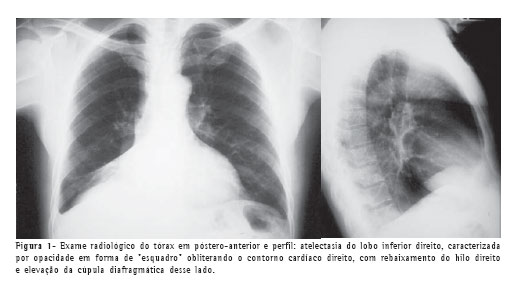

As radiografias do tórax nas incidências póstero-anterior e perfil evidenciaram sinais de redução volumétrica do lobo inferior direito, com borramento do contorno cardíaco desse lado (Figura 1).